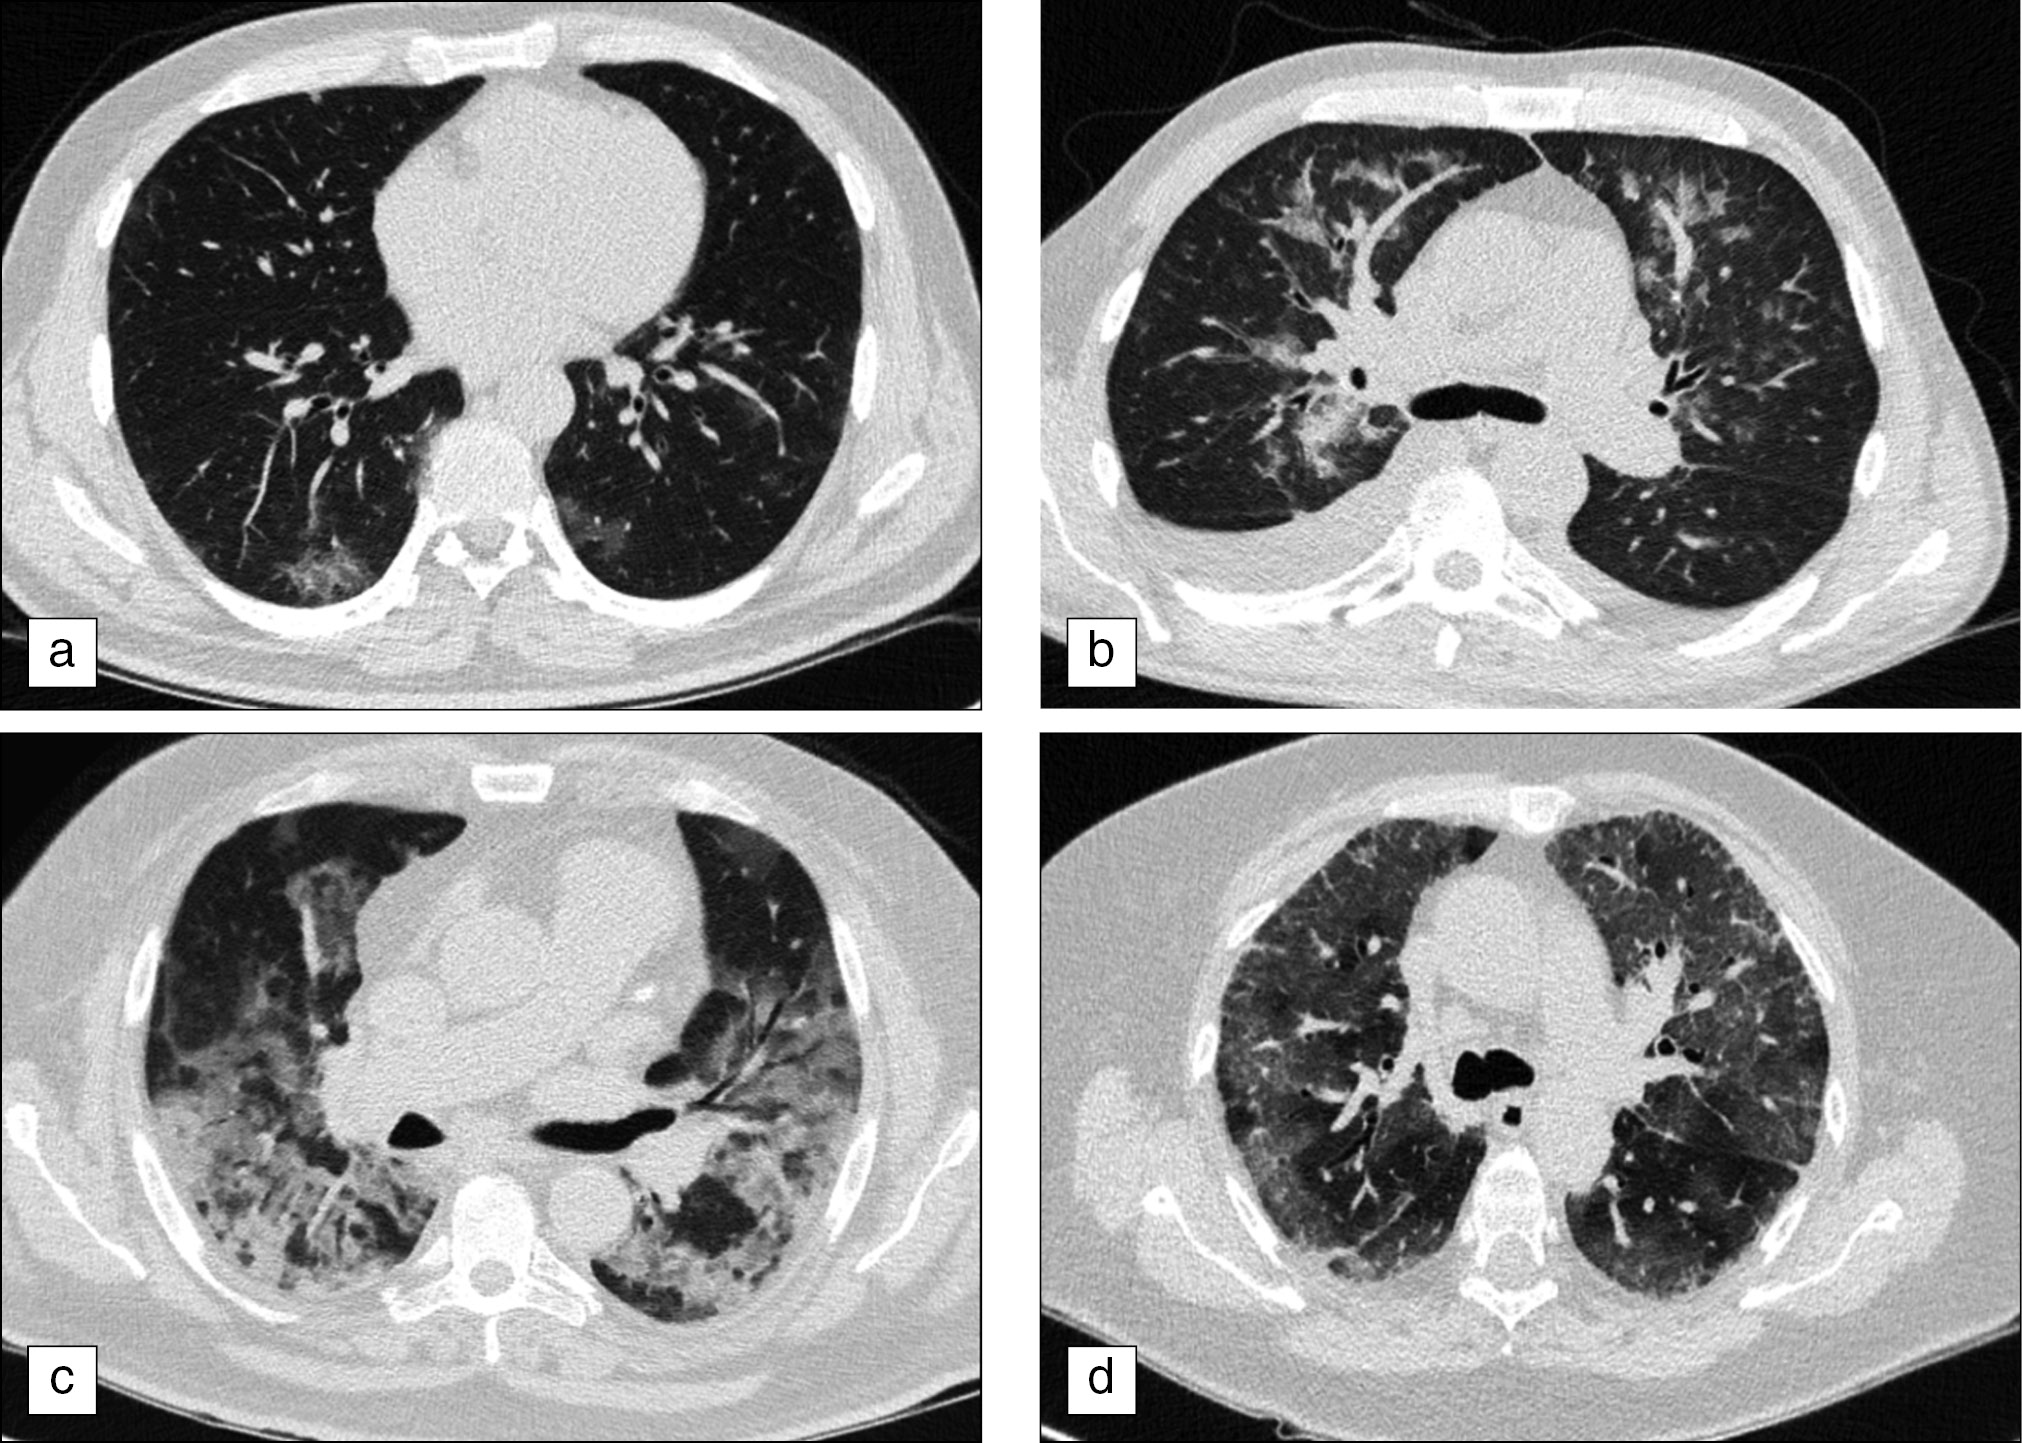

The severity of viral pneumonia according to the CT of the thoracic organs was mild in 38.5% of cases (Fig. 5, a), moderate in 46.2% (Fig. 5, b), severe in 12.3% (Fig. 5, c), and extremely severe in 3.1% of cases (Fig. 5, d).

Fig. 5. Viral pneumonia severity according to the computed tomography of the thoracic organs: a ― mild changes (CT-1), involvement of the lung parenchyma by ≤25%; b ― moderate changes (CT-2), involvement of the lung parenchyma by 25%–50%; c ― severe changes (CT-3), involvement of the lung parenchyma by 50%–75%; d ― extremely severe and critical changes (CT-4), involvement of the lung parenchyma by ≥75%.